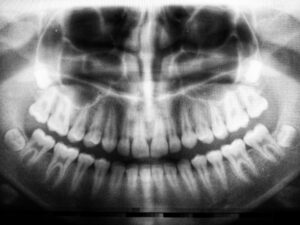

A panoramic dental X-ray provides a broad view of the entire mouth in a single […]

Panoramic dental X-rays are a valuable diagnostic tool in oral healthcare, offering a complete view […]

Panoramic dental X-rays are a type of imaging that captures a complete view of the […]

A panoramic dental X-ray is an important step in maintaining good oral health and preparing […]

Dental health plays an essential role in overall well-being, and one of the most useful […]

Dental health is a crucial aspect of overall well-being, and modern technology has made it […]

Panoramic dental X-rays have become an essential diagnostic tool in modern dentistry. These advanced images […]